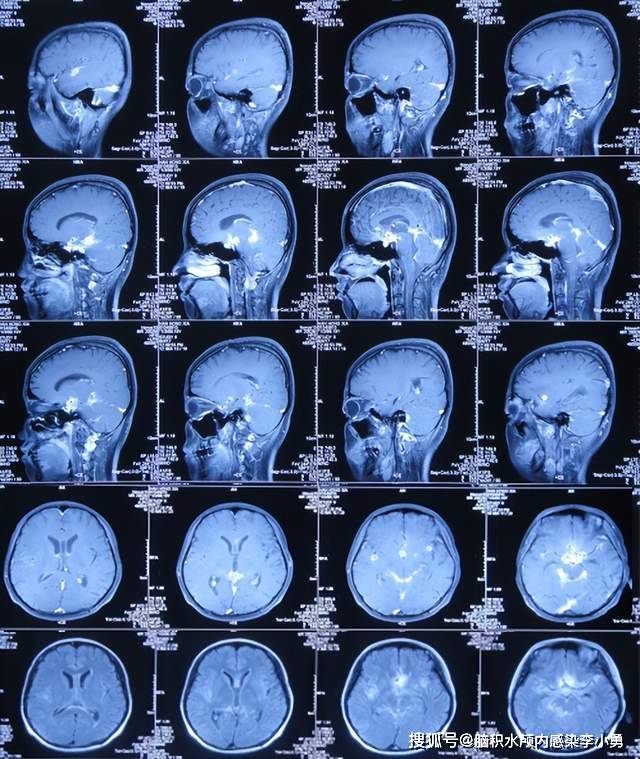

贺晓生教授谈小儿脑病:警惕化脓性脑膜炎后遗硬膜下积液患儿. (原创)

近致命性结核脑膜炎性脑积水发病后2个月内先后经4家医院治后仍无改善